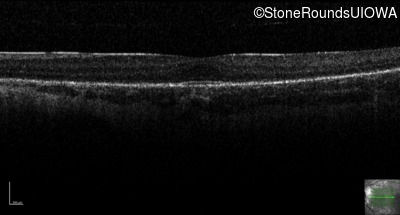

Optical Coherence Tomography - Right - 20/50 +1 sc

Exemplar / OCT Stack